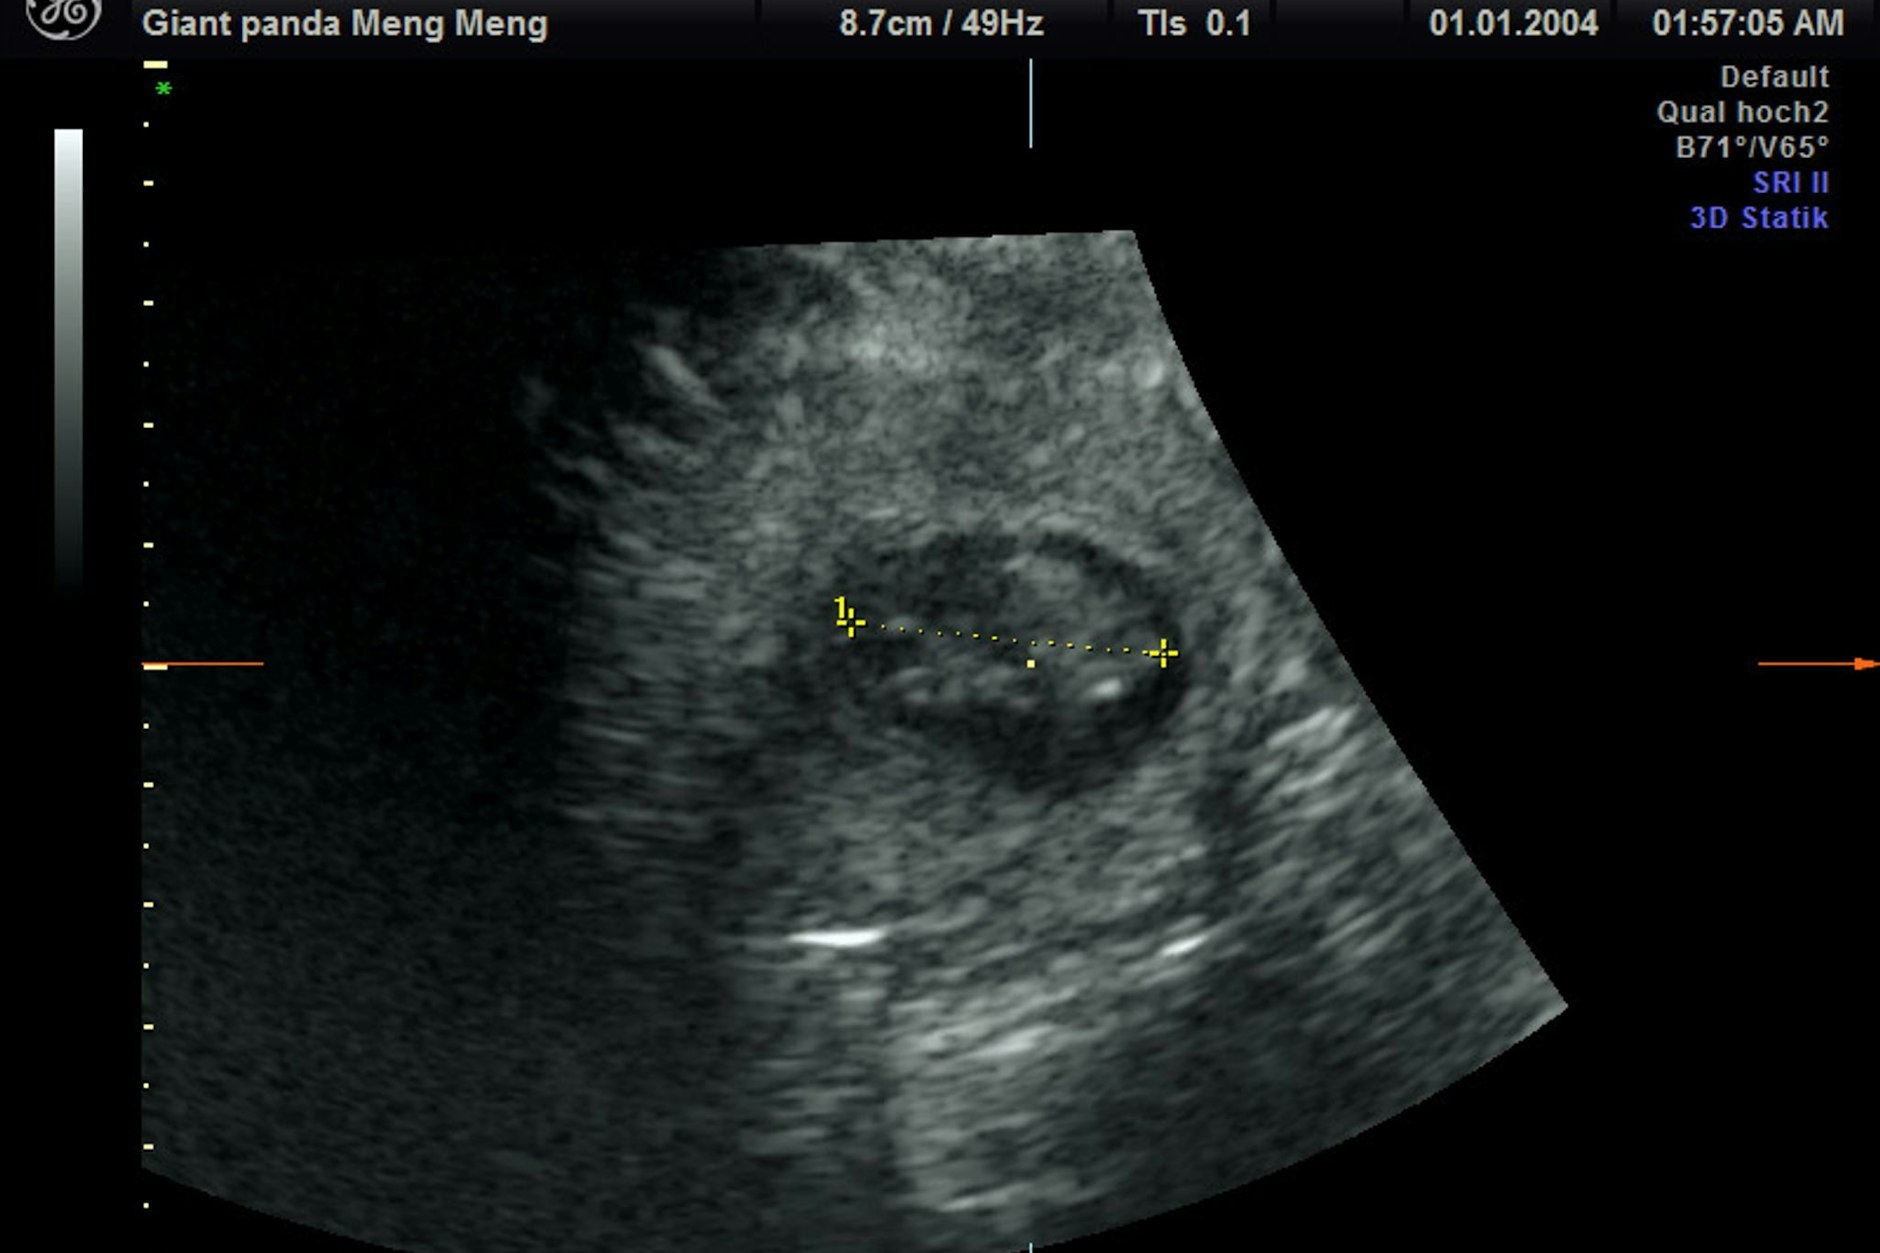

Schließlich klappte es doch: „Trotz sichtlichen Bauchkneifens“ habe Meng Meng sich überzeugen lassen, „in den aufrechten Stand zu kommen und das kühle Ultraschall-Gel sowie die Untersuchung mit der Ultraschall-Sonde zu akzeptieren“, sagte Hildebrandt. „Eine Untersuchung im Stehen hat schließlich die freudige Nachricht gebracht, dass Meng Meng mit zwei Jungtieren trächtig ist.“

Die Freude im Team sei riesig gewesen, weil es schon einige erfolglose Ultraschallversuche gegeben habe, sagte Zootierärztin Franziska Sutter, die ebenfalls an der Untersuchung beteiligt war. „Bei aller Begeisterung müssen wir uns darüber im Klaren sein, dass das ein sehr frühes Stadium der Trächtigkeit ist und eine sogenannte Resorption – also ein Absterben - des Embryos zu diesem Zeitpunkt noch möglich ist“, sagte Sutter. Die Tragzeit beträgt bei Großen Pandas in der Regel drei bis sechs Monate.